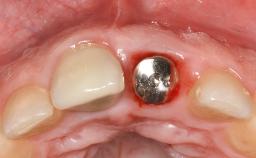

Treatment of Peri-Implantitis at a Zirconia Implant

Due to their promising clinical performance, zirconia implants have recently become popular alternatives to titanium implants, particularly for areas with high esthetic demands (Holländer and coworkers 2016; Roehling and coworkers 2016; Lorenz and coworkers 2019). However, regardless of the reported high survival and success rates, zirconia implants were affected by peri-implant diseases over the short observation period, suggesting the importance of treating peri-implant diseases at zirconia implants (Becker and coworkers 2017). In their case, Frank Schwarz and Ausra Ramanauskaite present 3-year results following mechanical debridement alongside Er:YAG laser monotherapy.